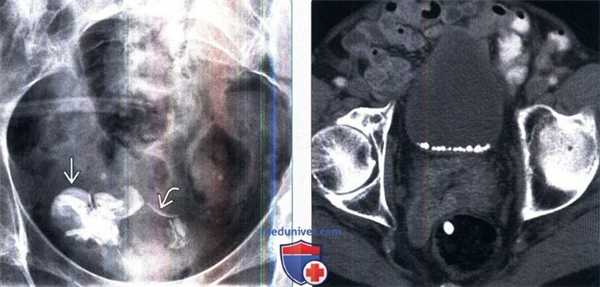

(Слева) Рентгенограмма женщины 37 лет с параплегией и микрогематурией в передней проекции: множественные камни в мочевом пузыре. Некоторые имеют индивидуальную криволинейную форму, что говорит о том, что они, возможно, сформированы вокруг инородных тел.

(Справа) КТ мочевого пузыря с контрастированием, аксиальный срез: множественные округлые кальцинированные камни, покрывающие нижнюю часть просвета мочевого пузыря. У пациента наблюдалась длительно текущая обструкция мочевого пузыря, вследствие доброкачественной гиперплазии простаты (ДГП).